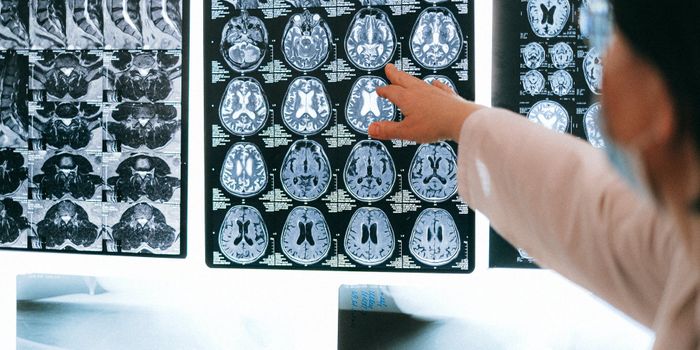

APR 03, 2018Clinical & Molecular DXScientists are improving the way PET scans work to detect diseases as early as possible with a new imaging agent. Focusi ...

DEC 03, 2020NeuroscienceTo obtain high-resolution images of the brain, researchers usually need to reduce the thickness of the skull or cut into ...

OCT 03, 2017NeuroscienceChronic traumatic encephalopathy (CTE) the brain disorder that experts agree is a result of repeated blows to the head t ...

JAN 22, 2016Clinical & Molecular DXTraumatic brain injuries kill about 50,000 Americans every year. To minimize mortality risks and speed up recovery time, ...